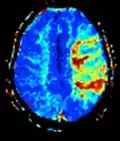

Neuroimagem

A ressonância magnética é a ferramenta investigativa de escolha para cânceres neurológicos, pois tem melhor resolução do que a TC e oferece uma melhor visualização da fossa posterior. O contraste fornecido entre matéria cinza e branca torna a ressonância magnética melhor opção para muitas condições do sistema nervoso central, incluindo doenças desmielinizantes, demência, doença cerebrovascular, doenças infecciosas e epilepsia.[30] Uma vez que muitas imagens são retiradas em milisegundos, mostra como o cérebro responde a diferentes estímulos, permitindo que os pesquisadores estudem as anormalidades cerebrais funcionais e estruturais em distúrbios psicológicos.[31] A RM também é utilizada na cirurgia estereotáxica guiada por MRI e radiocirurgia para o tratamento de tumores intracranianos, malformações arteriovenosas e outras condições tratáveis cirurgicamente usando um dispositivo conhecido como N-localizer.[32][33][34][35][36][37][38][39][40][41][42][43][44][45]